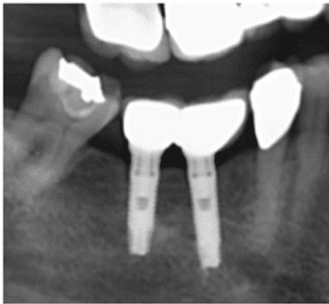

Cette technique sûre et efficace s’appuie sur des données scientifiques avec un recul clinique de plus de 20 ans. La pose d’un implant, réalisée sous anesthésie locale, est totalement indolore. Elle se pratique au cabinet dentaire ou en clinique. Le choix se fait en fonction de l’emplacement, de la quantité d’os disponible, et des éléments anatomiques environnants à partir d’un examen radiologique et scanner de la zone à implanter.

L’implant est placé dans l’os le plus souvent par vissage et doit avoir une forte stabilité dans l’os.

Il faut attendre après la pose de l’implant, l’ostéo intégration, qui peut durer plusieurs mois.

L’implant va se souder complètement avec l’os et contrairement à la dent il n’y a pas de ligament alvéolo-dentaire.